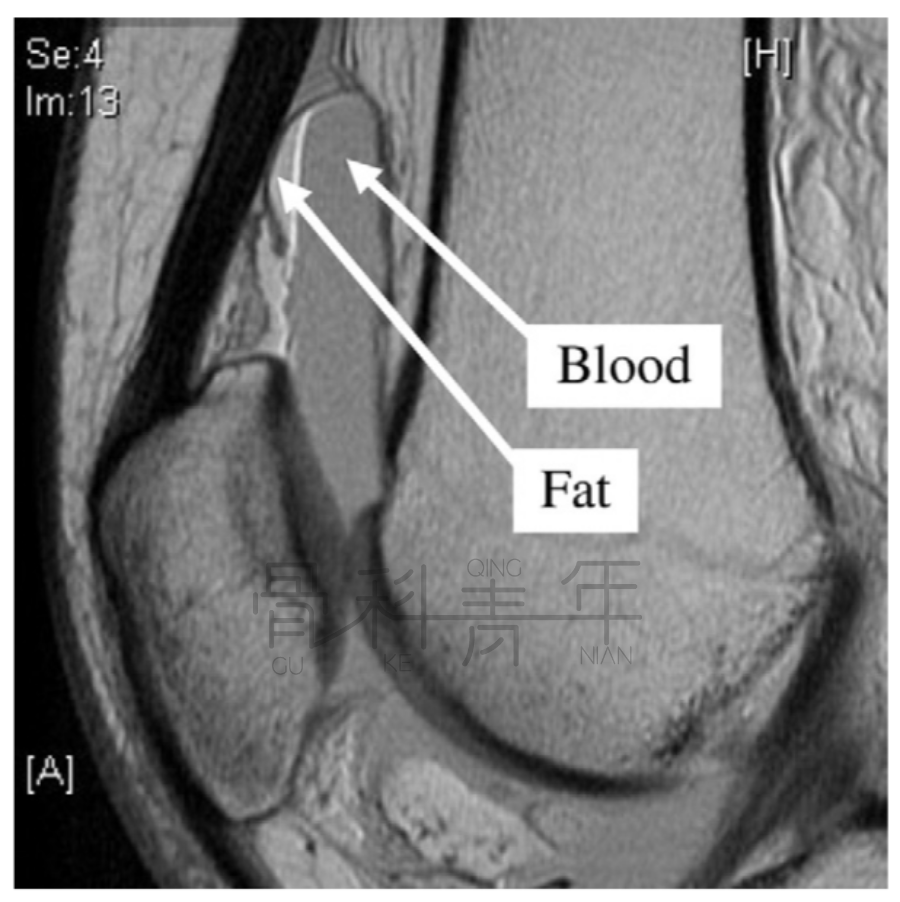

病例2一例左膝外伤患者。在MR横断与矢状位上均可见明显液体分层(见箭头所示)。